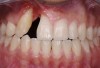

Successful outcomes with forced eruption require the establishment of treatment endpoints, which may include overcompensation beyond the desired soft- and hard-tissue changes. For the present case, achieving ideal gingival-alveolar socket architecture required force-erupting tooth No. 6 to the level of the apical third and tooth No. 8 beyond the confines of its alveolus. As the gingival sulcus is everted through the eruption process, a gingival red patch corresponding to the nonkeratinized sulcular epithelium may appear, as shown around tooth No. 8 in Figure 8 and Figure 9. This tissue will develop into keratinized gingiva when exposed to the oral environment.31,32 Additionally, when forced eruption of this magnitude is performed, there may be a tendency for lingual displacement that needs to be addressed with root-torquing orthodontic auxiliaries (Figure 6 and Figure 7).

When forced eruption is completed, the teeth should be splinted for a 3-month stabilization period,30 which will allow mineralization of osteoid tissue and settling of the gingival remodeling process. The degree of forced eruption in the present case was such that extreme mobility precluded the use of a provisional restoration. Instead, a metal-reinforced direct composite splint extending from teeth Nos. 6 to 8 was fabricated in situ (Figure 8 and Figure 9). When compared with the preoperative condition (Figure 2), Figure 8 and Figure 9 depict the treatment progression with forced eruption. The restoration of adequate alveolar height was achieved while enhancing the soft-tissue architecture, and the everted sulcular epithelium on tooth No. 8 proceeded to develop keratinization. However, the pre-existing defect still manifested itself in the form of a residual cleft.

Fig 8. Compared to the preoperative view seen in Fig 2, adequate alveolar height and gingival profile were achieved with forced eruption (Fig 8). Direct composite splint would remain for 3 months. Residual cleft was a visible remnant of iatrogenic defect. Post-orthodontically, keratinization of sulcular epithelium on tooth No. 8 was evident (Fig 9).

Figure 8

Fig 9. Compared to the preoperative view seen in Fig 2, adequate alveolar height and gingival profile were achieved with forced eruption (Fig 8). Direct composite splint would remain for 3 months. Residual cleft was a visible remnant of iatrogenic defect. Post-orthodontically, keratinization of sulcular epithelium on tooth No. 8 was evident (Fig 9).

Figure 9